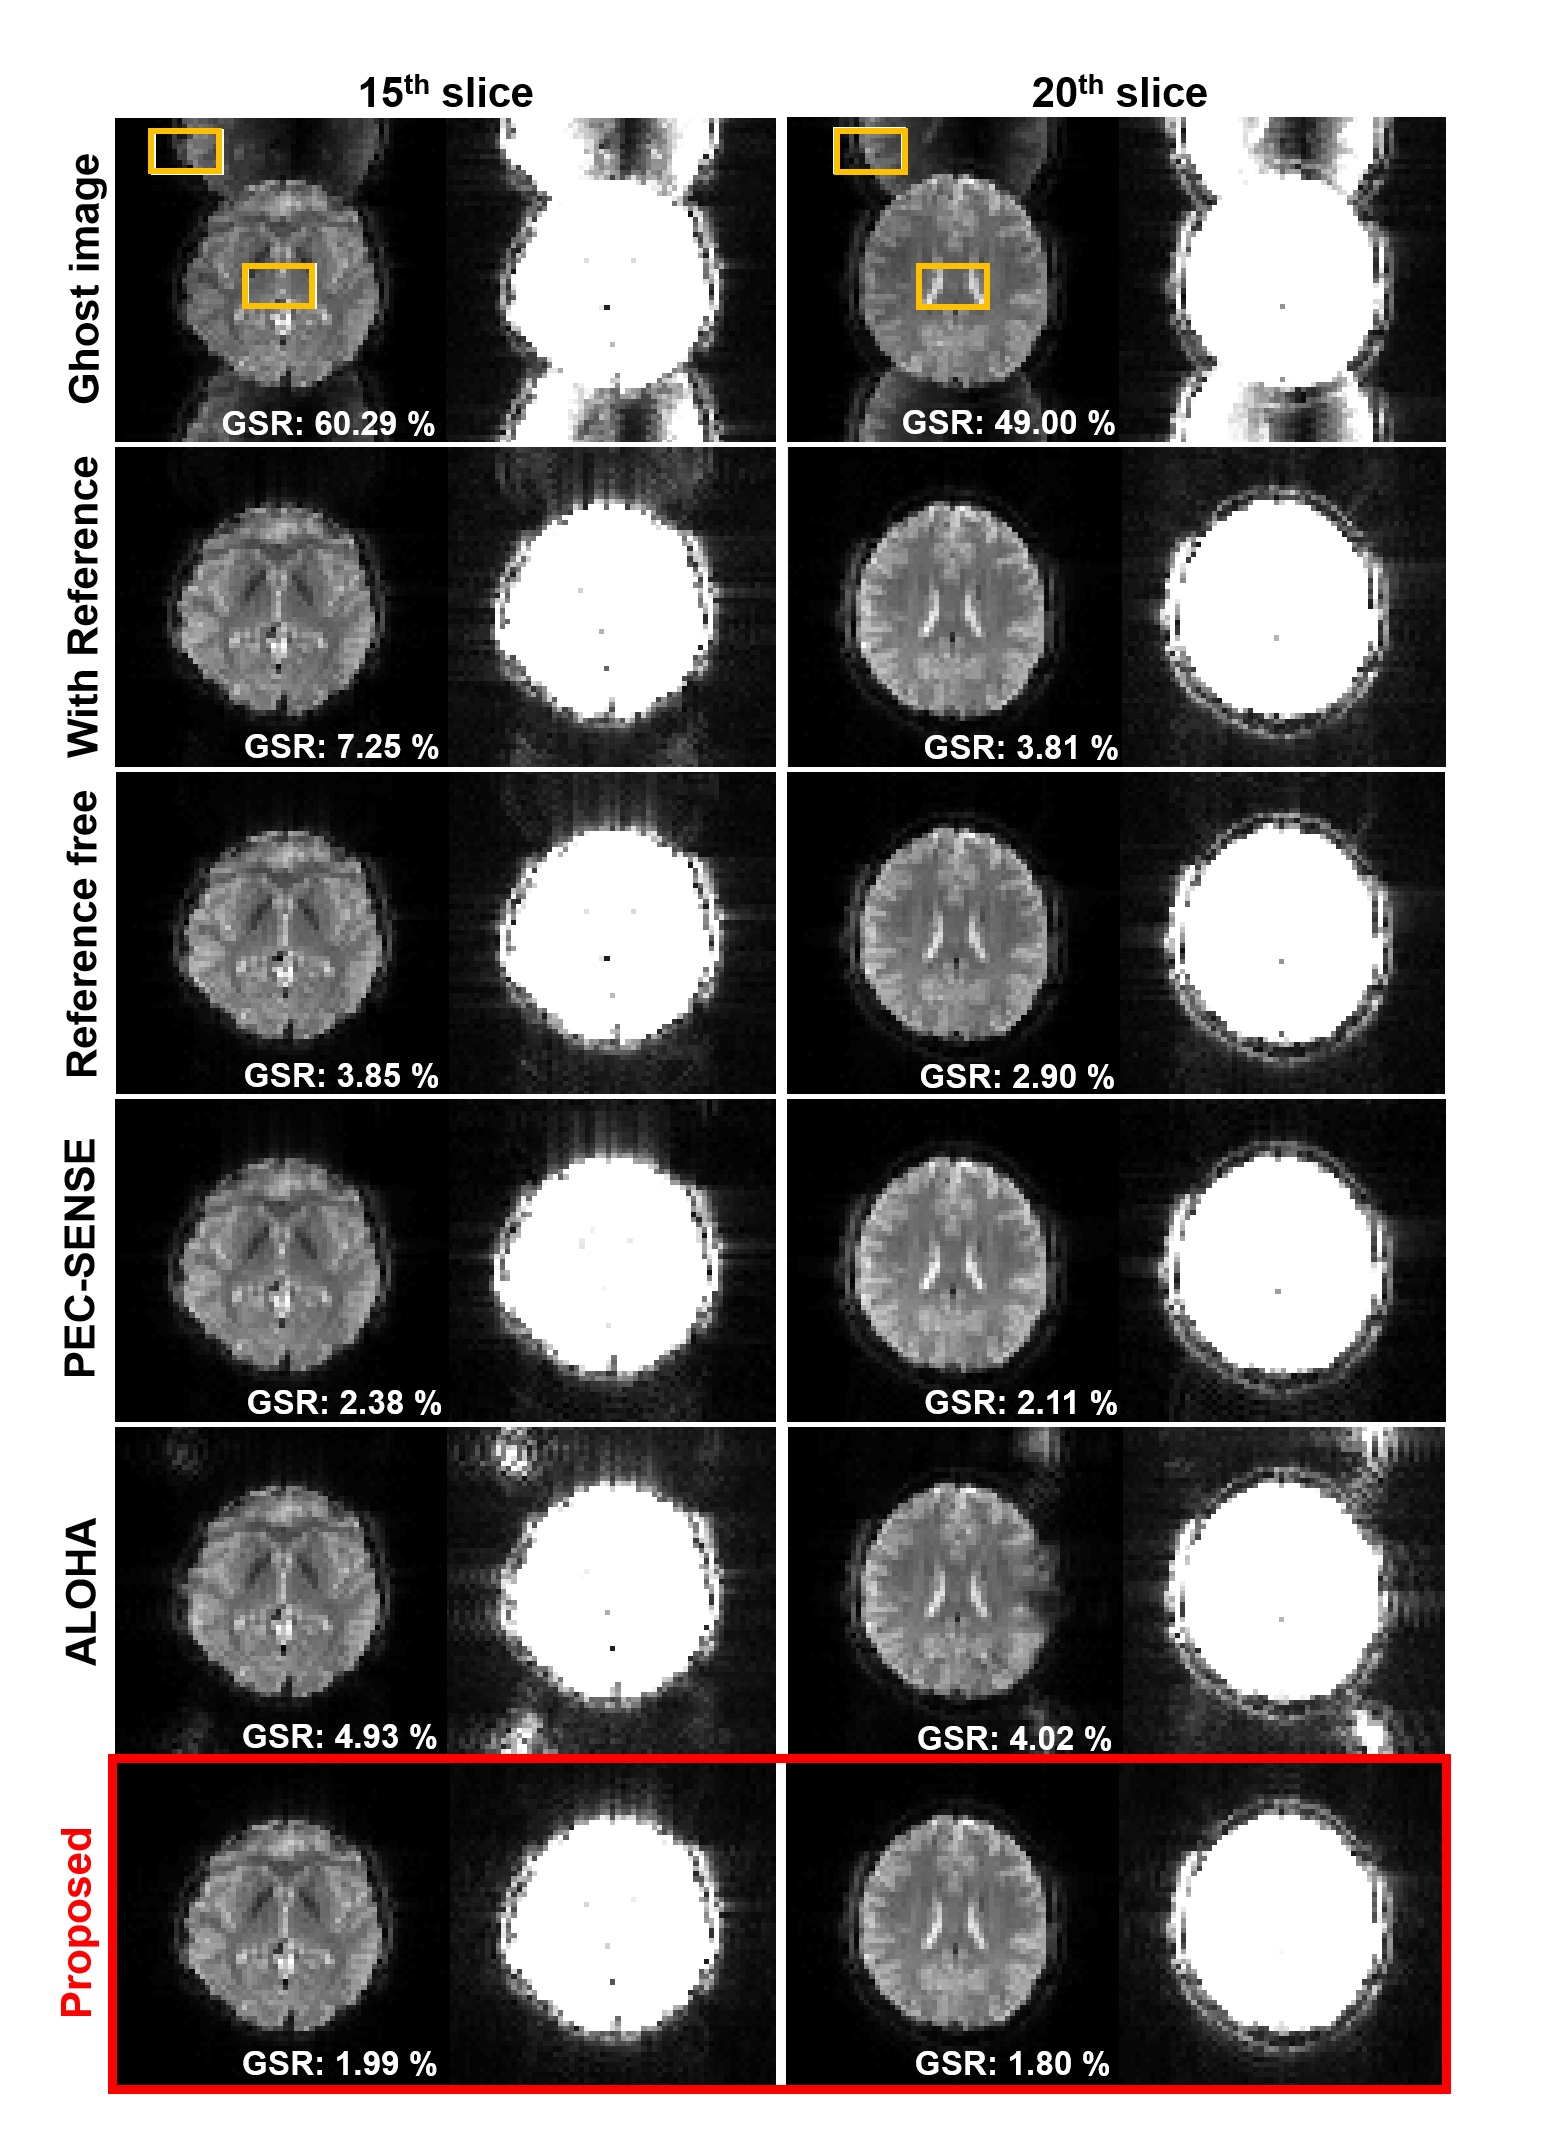

The results for 3T EPI ghost correction is shown in Fig. 5. The intensity re-scaled result images are also shown in the figure. In order to observe the remaining ghost more concisely, the image scale was re-scaled at 5 times of original intensity. The reconstruction performance of various ghost correction methods are mostly good in 3T EPI data, but slightly remaining ghost artifact can be seen in the intensity magnified images from the conventional methods. Now, Fig. 6 shows the 7T EPI ghost correction result with corresponding 5 times increase in brightness image. Most correction methods except the proposed method shows a remaining ghost artifact. Furthermore, Fig. 6 confirmed that the proposed method for accelerated EPI data (see Fig. 3(a)) can accurately correct ghost artifacts and provide visually similar results from the network in Fig. 3(b) that explicitly utilizes the GRAPPA kernel estimation steps.

To compare the result quantitatively, we calculate the ghost to signal ratio and mark ghost-to-signal ratio (GSR) value on the result figure. The GSR values corresponding to each result are calculated using regions represented by the yellow boxes and marked on the image. As shown in this result, the proposed method successfully removed ghost artifacts and shows the lowest GSR value. Although the performance of the PEC-SENSE which uses the parallel imaging information is better than the other existing methods, the GSR value was higher than the proposed method. Moreover, the proposed method using Fig. 3(a) provides much smaller GSR values than the network training using Fig. 3(b).